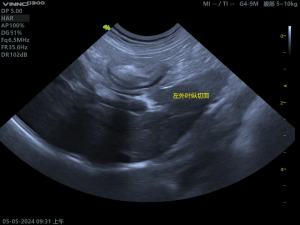

(2)胆囊粘液囊肿影像

胆囊内呈现“猕猴桃征”或“星芒状”的回声。胆囊壁增厚、胆泥淤积、可评估胆囊是否破裂。